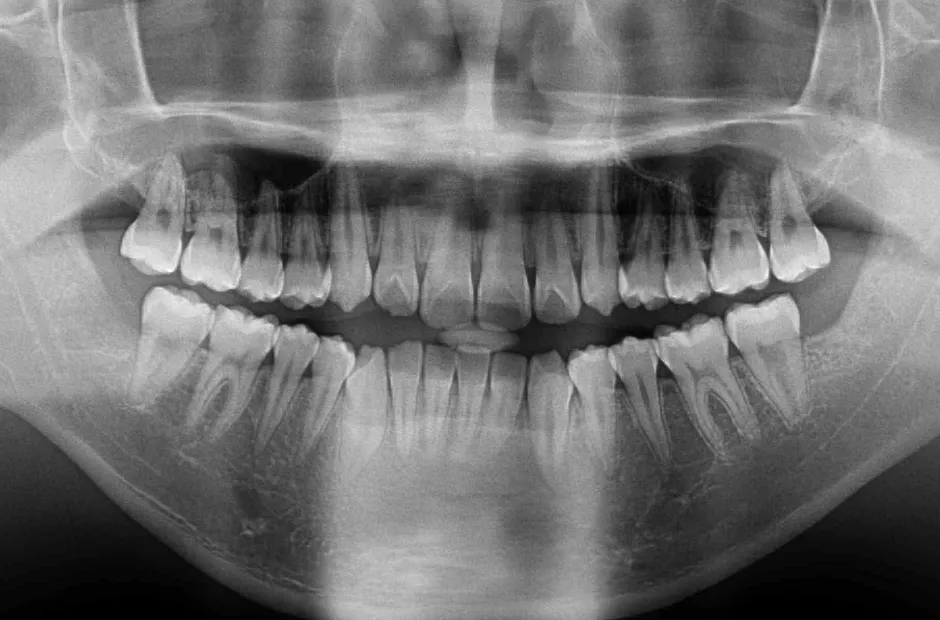

叢生

| 診断名・主訴 | 叢生 |

|---|---|

| 年齢・性別 | 43歳・女性 |

| 治療期間・回数 | 2年7か月 27回 |

| 治療に用いた主な装置 | 舌側矯正 |

| 抜歯部位 | 両顎4,4 |

| 治療費 | 100万円(税抜) |

| リスク・副作用 | 装置による違和感・疼痛・歯肉退縮・歯根吸収・虫歯のリスクなど |

治療前

治療中